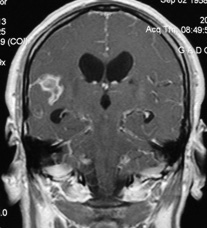

En la RM cerebral, los tuberculomas muestran lesiones realzadas en anillo después de la administración de contraste, que es heterogénea al igual que en un glioma y dependerá de la fase de evolución de las lesiones (7,8,13). La afectación de los pares craneales, el resultado de infiltración meníngea difusa, la localización preferentemente basilar y las lesiones tanto supratentoriales e infratentoriales contribuyen en el diagnóstico de la TBC (13,14-17). En casos de leptomeningitis tuberculosa, el contraste paramagnético en la RM muestra generalmente un engrosamiento meníngeo. Las imágenes de transferencia de magnetización que muestra el menor contenido proteico del tuberculoma y el nuevo protocolo de imágenes de transferencia de protones de amida ayudarían para la difícil diferenciación de tuberculomas de gliomas de alto grado (18). La intervención quirúrgica estaría indicada cuando exista incertidumbre diagnóstica, gran efecto de masa y mala respuesta a la prueba terapéutica (19).

En la figura 1, se presenta la imagen de una RM en corte coronal, ponderada en TW-1, con gadolinio que muestra captación leptomeningea por meningitis, un granuloma tuberculoso adyacente al valle silviano derecho y la expansión de los ventrículos laterales por hipertensión endocraneana.